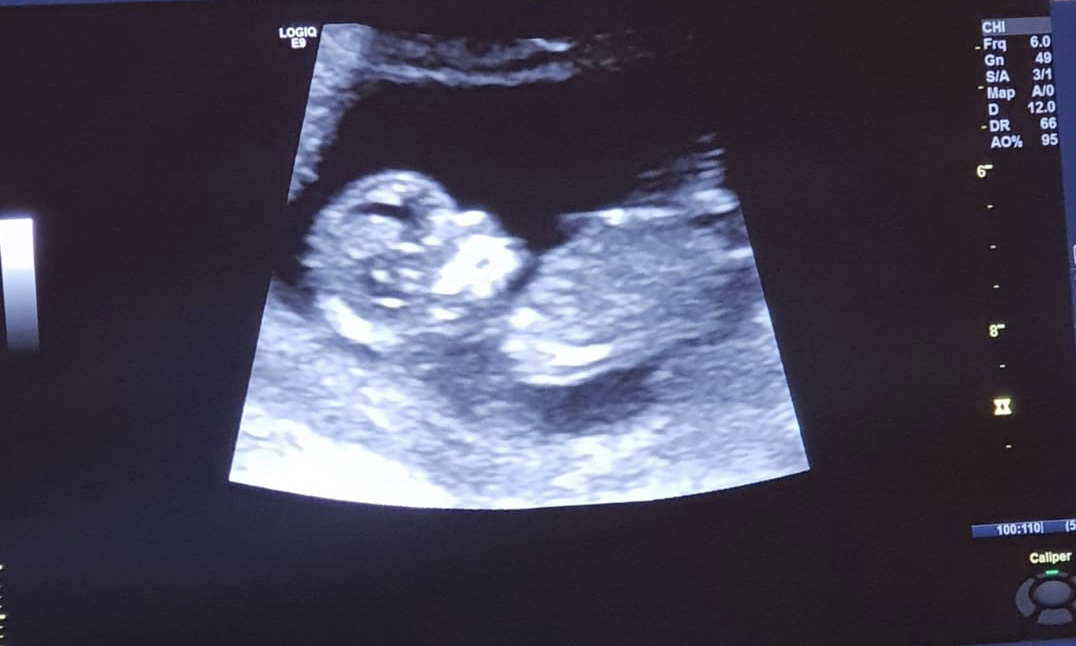

FYI this was my DD at 12 weeks

Attachment 43269